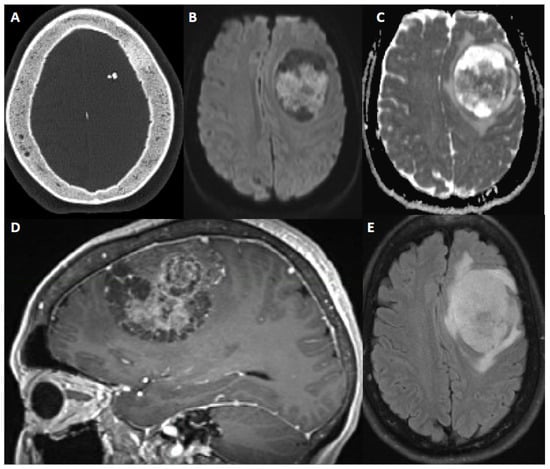

Figure 3. 60-year-old female with new onset seizure, nausea, vomiting, and headache. After resection, pathology showed atypical meningioma, WHO grade 2. Molecular markers: TERT promoter wild type, positive for chromosome 8 and 22 loss (haploinsufficiency of NF2). (A) Axial CT head shows calcification within a mass and sclerosis of the overlying calvarium. (B,C) DWI and ADC map show restricted diffusion within the extra-axial mass. (D) Sagittal contrast-enhanced Magnetization Prepared-RApid Gradient Echo (MPRAGE) shows a heterogeneously enhancing multicystic dural-based mass with moderate mass effect. (E) Axial fluid attenuated inversion recovery (FLAIR) sequence shows moderate surrounding vasogenic edema.